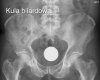

Ludzie to niesamowity gatunek. Potrafią tworzyć niesamowite rzeczy, ale jednocześnie potrafią być równie skretyniali co inteligentni. Mamy dla Was galerię niesamowitych szpitalnych zdjęć rentgenowskich na których uwieczniono człowieka i narzędzie zbrodni. Nigdy nie uwierzycie jakie przedmioty ludzie wkładają sobie w tyłek!